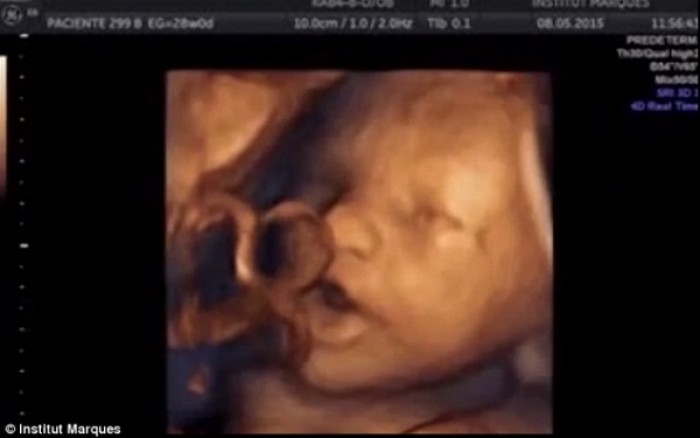

Ο υπέρηχος πριν ξεκινήσει η μουσική έδειξε ότι περίπου το 45% των εμβρύων κινούσαν αυθόρμητα το κεφάλι και τα άκρα τους, ενώ ποσοστό περίπου 30% κινούσαν το στόμα ή τη γλώσσα τους. Περίπου το 10% των εμβρύων έβγαζαν τη γλώσσα τους έξω από το στόμα. Όταν τα μωρά άκουσαν τη μουσική (ενδοκολπικά), το συντριπτικό 87% ανταποκρίθηκε κουνώντας το κεφάλι και τα άκρα. Οι κινήσεις αυτές συνοδεύονταν μάλιστα από συγκεκριμένες κινήσεις του στόματος και της γλώσσας οι οποίες σταματούσαν όταν σταματούσε και η μουσική.